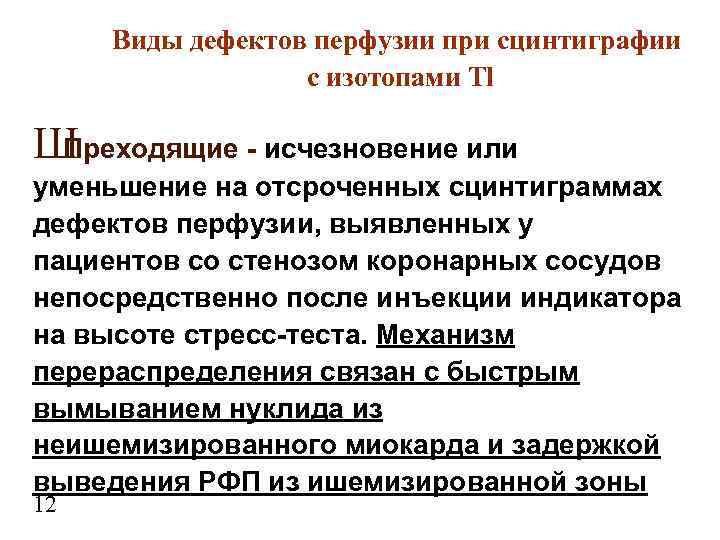

Виды дефектов перфузии при сцинтиграфии с изотопами Tl Ш Преходящие - исчезновение или уменьшение на отсроченных сцинтиграммах дефектов перфузии, выявленных у пациентов со стенозом коронарных сосудов непосредственно после инъекции индикатора на высоте стресс-теста. Механизм перераспределения связан с быстрым вымыванием нуклида из неишемизированного миокарда и задержкой выведения РФП из ишемизированной зоны 12

Виды дефектов перфузии при сцинтиграфии с изотопами Tl Ш Преходящие - исчезновение или уменьшение на отсроченных сцинтиграммах дефектов перфузии, выявленных у пациентов со стенозом коронарных сосудов непосредственно после инъекции индикатора на высоте стресс-теста. Механизм перераспределения связан с быстрым вымыванием нуклида из неишемизированного миокарда и задержкой выведения РФП из ишемизированной зоны 12